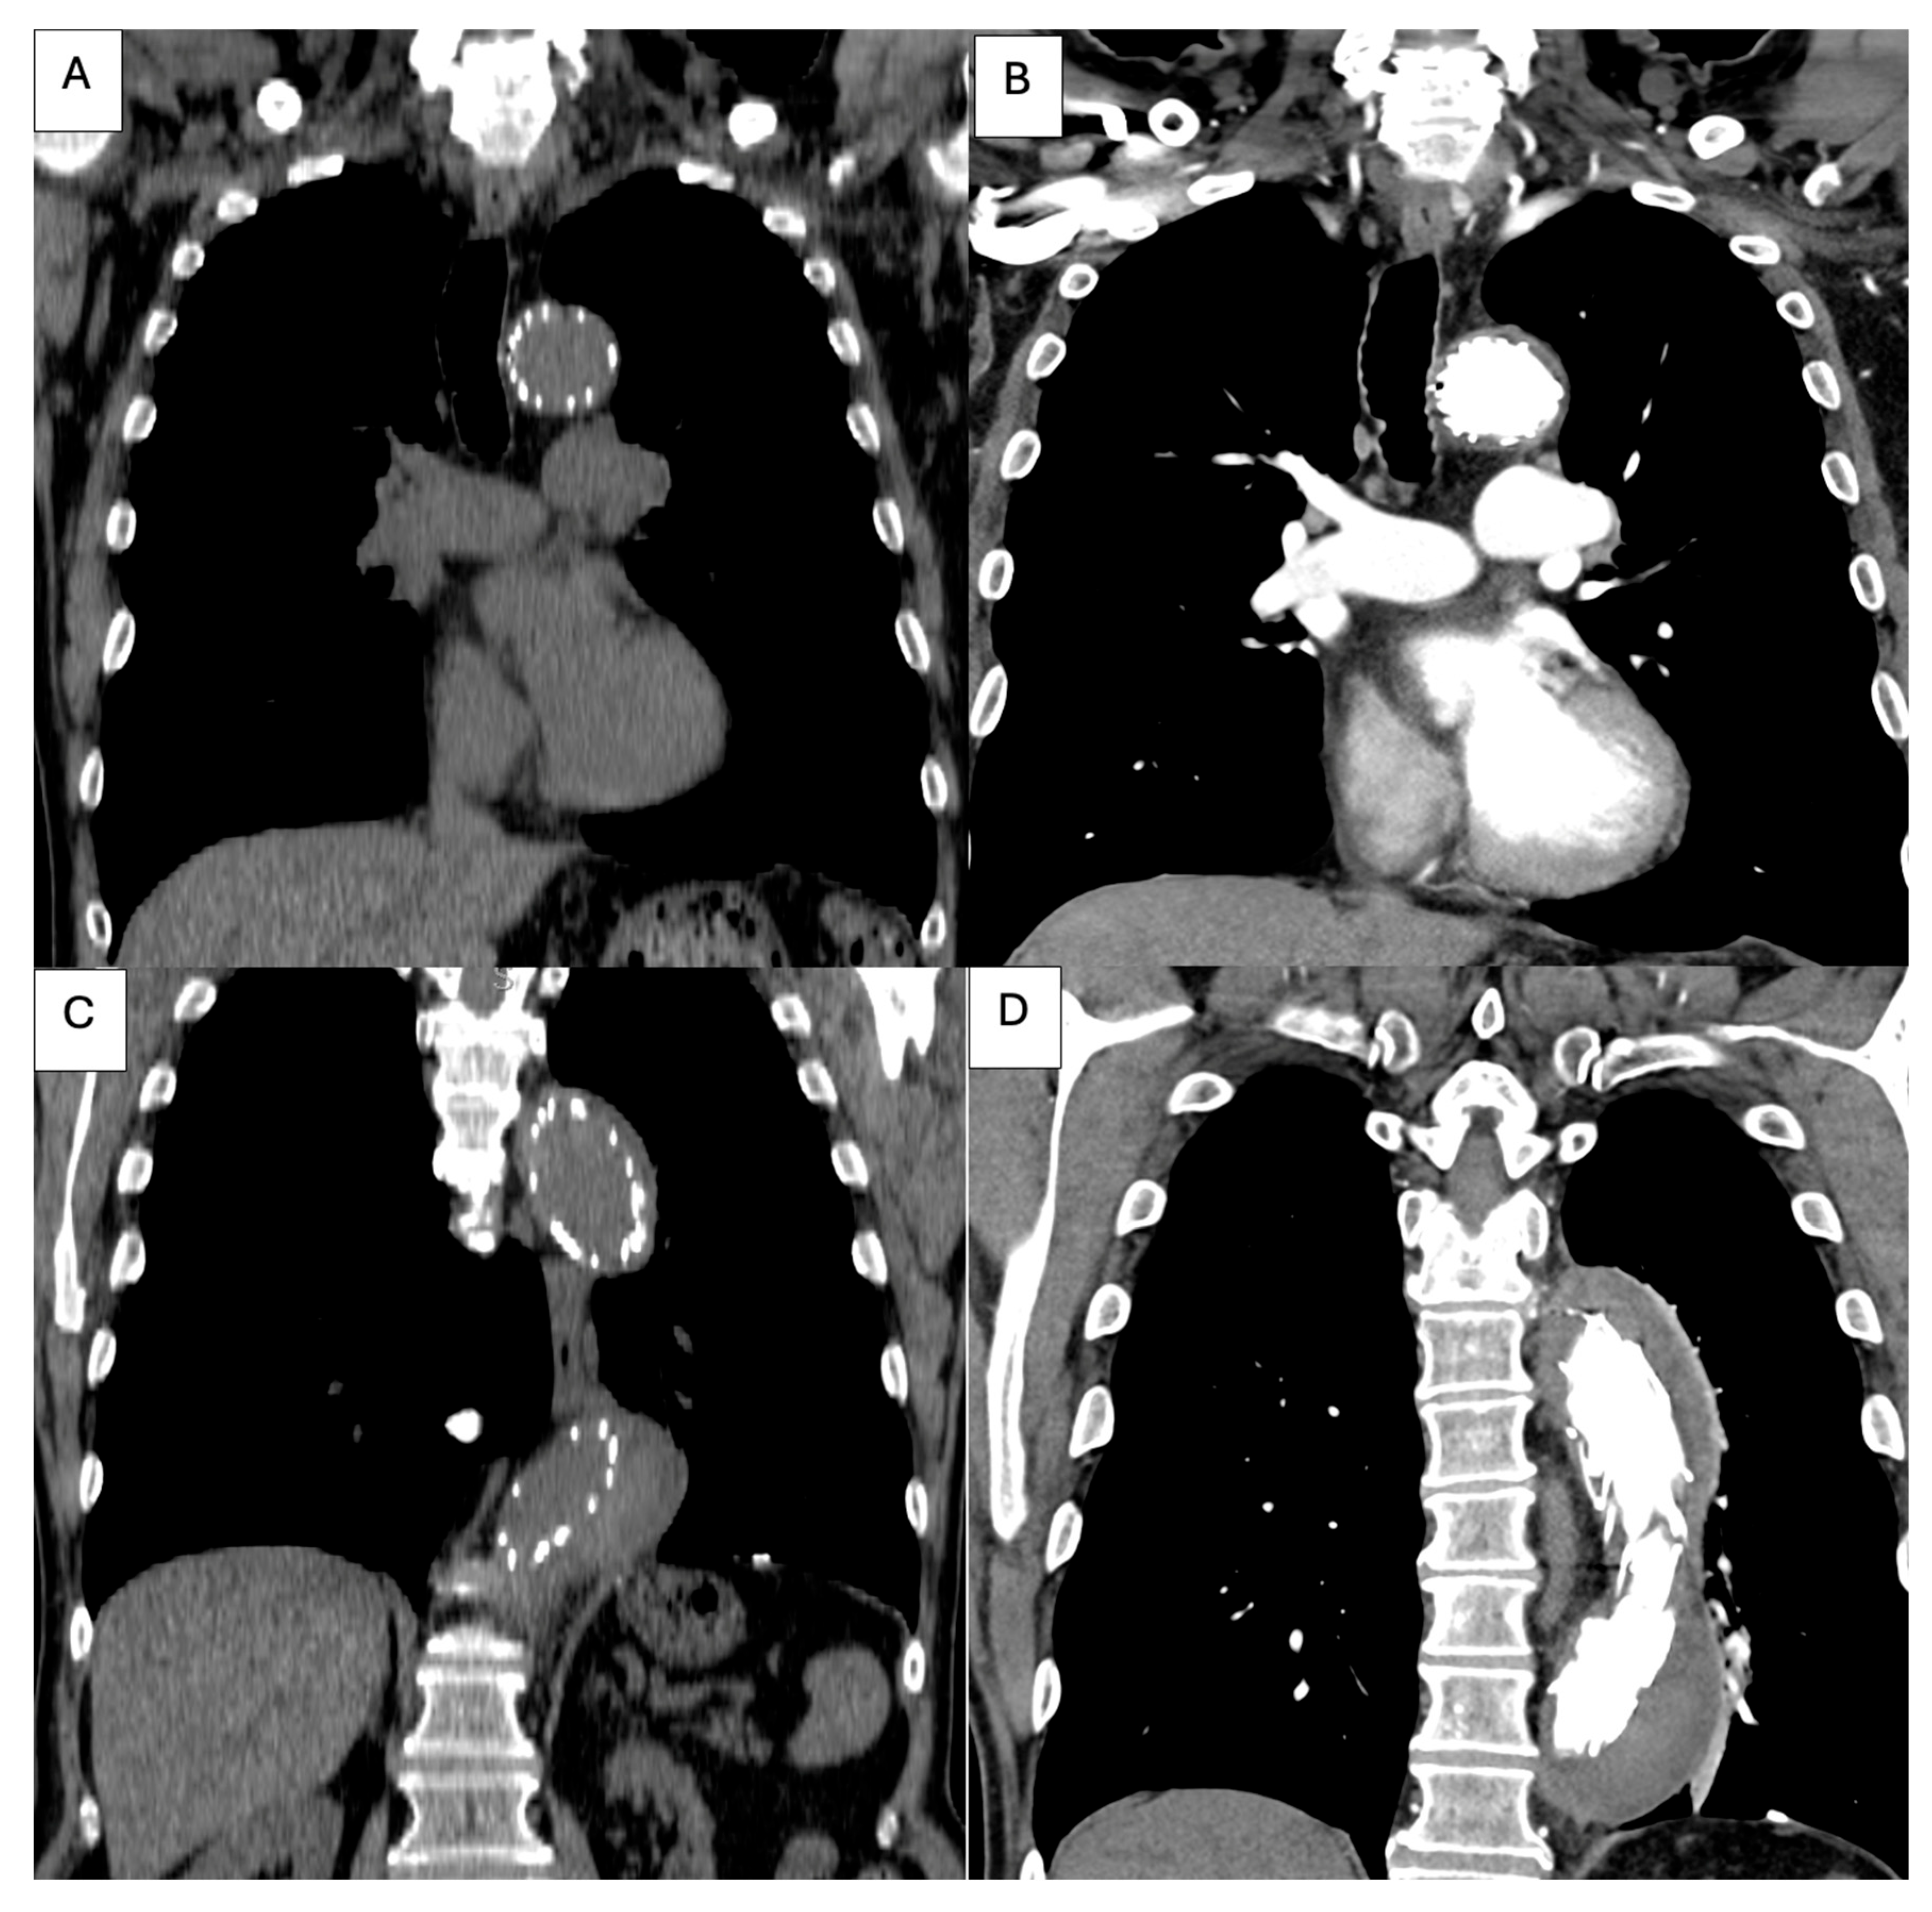

| True lumen | Severely compressed along descending thoracic and abdominal aorta | Re-expanded across thoracic segment | Stable re-expansion |

| Visceral perfusion | SMA and celiac from severely collapsed TL; R renal from FL | TL restored at visceral segment; R renal improved inflow | Full visceral patency; no endoleak |